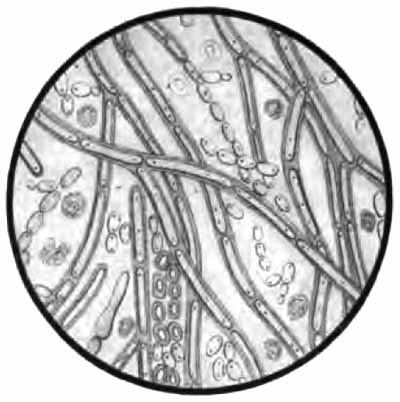

6. Molds.—The hyphæ and spores of various molds are occasionally met with in the sputum. They are usually the result of contamination, and have little significance. The hyphæ are rods, usually jointed or branched (Fig. 58), and often arranged in a meshwork (mycelium); the spores are highly refractive spheres. Both stain well with the ordinary stains.

The more important structures to be seen in unstained sputum are: elastic fibers, Curschmann's spirals, [p. 27] Charcot-Leyden crystals, fibrinous casts, the ray fungus of actinomycosis, and molds. Pigmented cells, especially the so-called "heart-failure cells" (p. 43), are also best studied without staining (Plate II, Fig. 1).